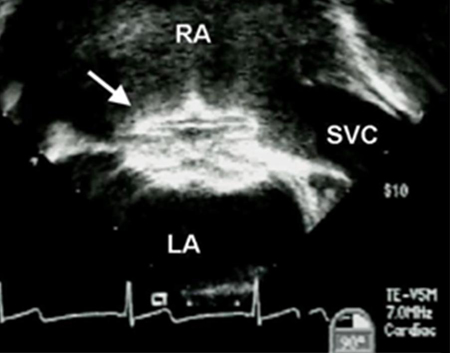

Imagem de ecocardiografia transesofágica de um dispositivo de oclusão de defeito do septo atrial (DSA) (seta). (AD) átrio direito; (AE) átrio esquerdo; (VCS) veia cava superior

Imagem cedida por Patrick W. O'Leary, MD